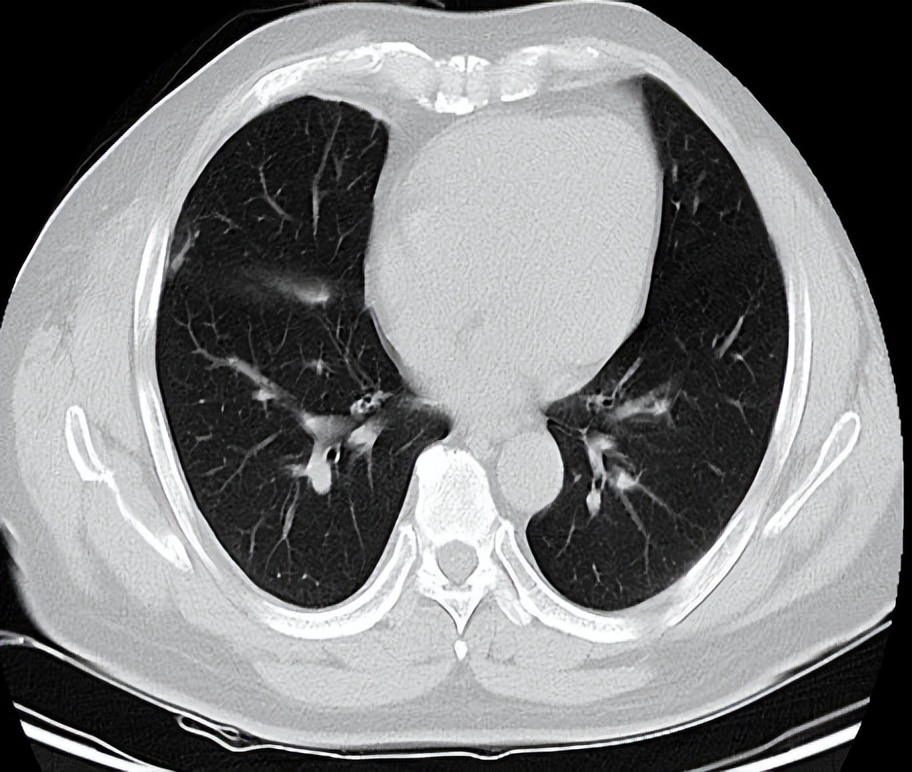

2021-5-21日入院后完善相关检查,胸部CT检查提示病灶进展,后予以化疗+抗血管治疗(白蛋白紫杉醇480mgd1+贝伐珠单抗600mg)治疗,并行右侧胸膜SBRT治疗(40Gy/5F),治疗周期为8周期,最佳疗效为PR。